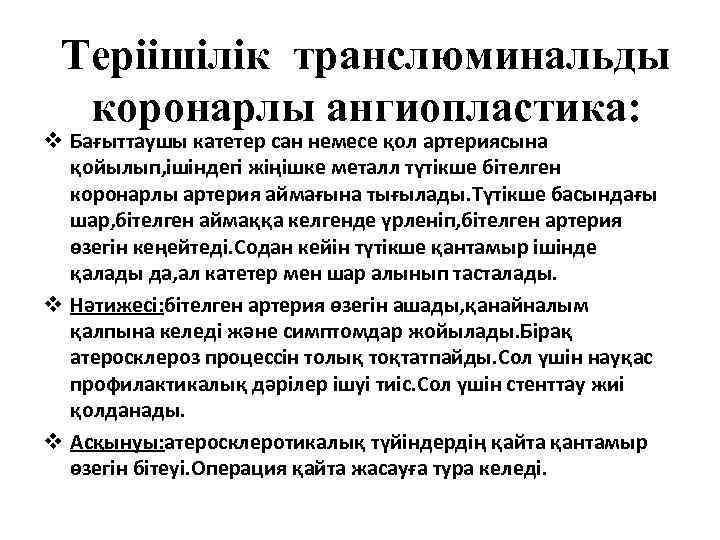

Теріішілік транслюминальды коронарлы ангиопластика: v Бағыттаушы катетер сан немесе қол артериясына қойылып, ішіндегі жіңішке металл түтікше бітелген коронарлы артерия аймағына тығылады. Түтікше басындағы шар, бітелген аймаққа келгенде үрленіп, бітелген артерия өзегін кеңейтеді. Содан кейін түтікше қантамыр ішінде қалады да, ал катетер мен шар алынып тасталады. v Нәтижесі: бітелген артерия өзегін ашады, қанайналым қалпына келеді және симптомдар жойылады. Бірақ атеросклероз процессін толық тоқтатпайды. Сол үшін науқас профилактикалық дәрілер ішуі тиіс. Сол үшін стенттау жиі қолданады. v Асқынуы: атеросклеротикалық түйіндердің қайта қантамыр өзегін бітеуі. Операция қайта жасауға тура келеді.

Теріішілік транслюминальды коронарлы ангиопластика: v Бағыттаушы катетер сан немесе қол артериясына қойылып, ішіндегі жіңішке металл түтікше бітелген коронарлы артерия аймағына тығылады. Түтікше басындағы шар, бітелген аймаққа келгенде үрленіп, бітелген артерия өзегін кеңейтеді. Содан кейін түтікше қантамыр ішінде қалады да, ал катетер мен шар алынып тасталады. v Нәтижесі: бітелген артерия өзегін ашады, қанайналым қалпына келеді және симптомдар жойылады. Бірақ атеросклероз процессін толық тоқтатпайды. Сол үшін науқас профилактикалық дәрілер ішуі тиіс. Сол үшін стенттау жиі қолданады. v Асқынуы: атеросклеротикалық түйіндердің қайта қантамыр өзегін бітеуі. Операция қайта жасауға тура келеді.